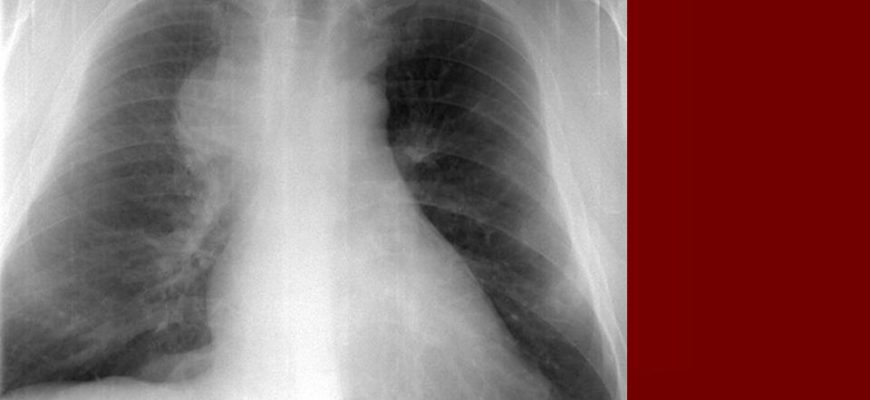

Из инструментальных обследований методом выбора является рентгенография грудной клетки. Изображение выполнено в двух проекциях. При медиастинальной форме рака легкого наблюдается расширение медиальной тени. В некоторых случаях можно увидеть очертания опухоли.

КТ и МРТ показывают большие конгломераты с волнистыми контурами. Позитронно-эмиссионная томография (ПЭТ) показывает скопление контрастного вещества в средостении.